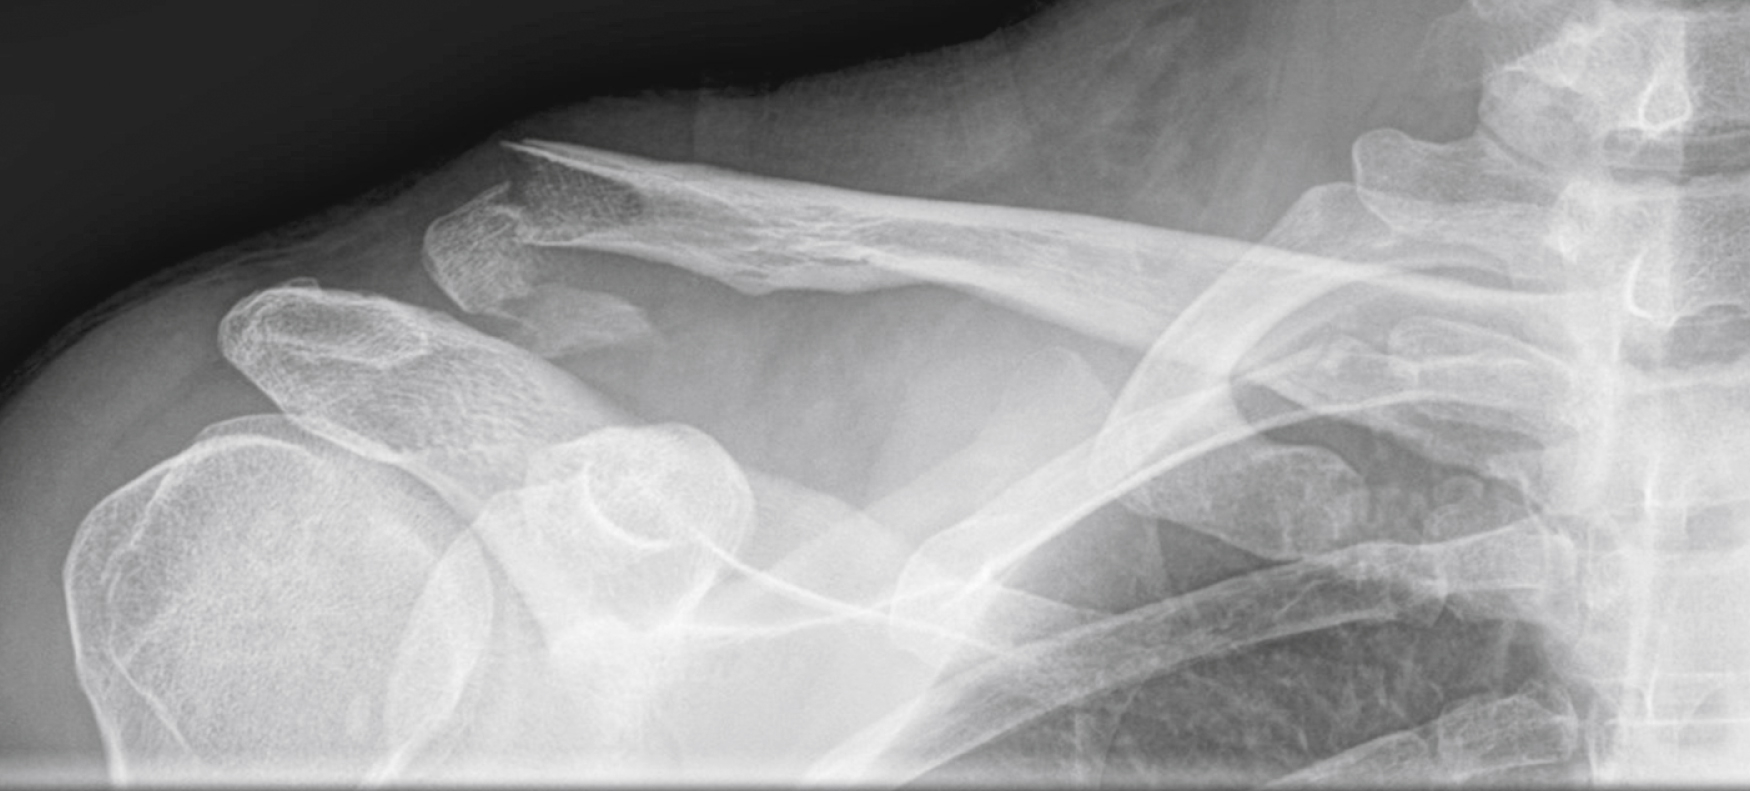

Scapular fractures are divided into two main types: extra-articular (neck [ Fig. 45.11 ], body, acromion process, coracoid process, spine) and intra-articular (with partial or total glenoid involvement).

Extra-Articular Fracture Involving the Neck of the Scapula.

Note the associated midclavicular fracture.